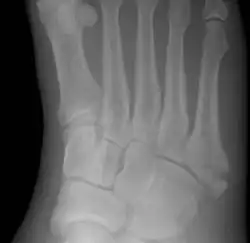

![]() | |

| Jones fracture as seen on Xray | |

A Jones fracture is a broken bone in a specific part of the fifth metatarsal of the foot between the base and middle part .[8] In general, fifth metatarsal fractures heal readily, but a Jones fracture must be recognized and accurately diagnosed because of its higher rate of delayed healing or nonunion.[4] It results in pain near the midportion of the foot on the outside.[2] There may also be bruising and difficulty walking.[3] Onset is generally sudden.[4]

The fracture typically occurs when the toes are pointed and the foot bends inwards.[6][2] This movement may occur when changing direction while the heel is off the ground such in dancing, tennis, or basketball.[9][10] Diagnosis is generally suspected based on symptoms and confirmed with X-rays.[3]

Diagnostic X-rays include anteroposterior, oblique, and lateral views and should be made with the foot in full flexion.